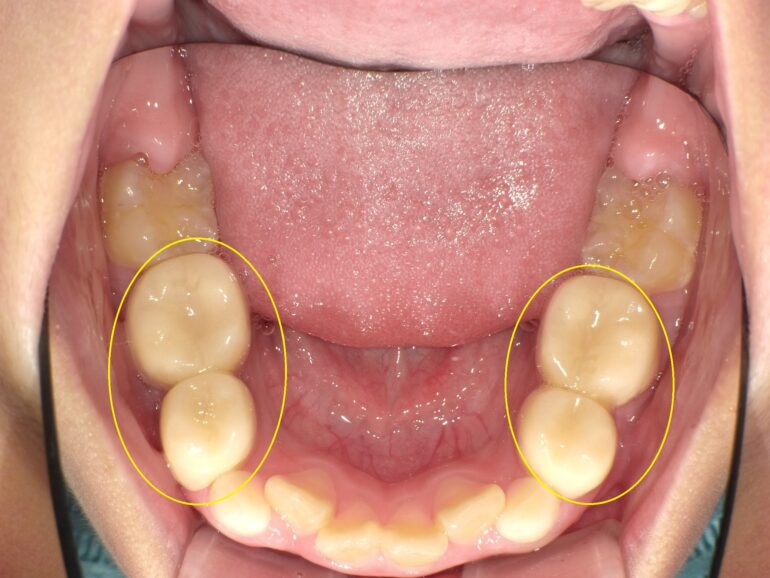

当院で行っている小児矯正『ネオキャップ、ビムラー矯正』は、

お子さんがもともと持っているお口の機能の成長発育を促すことにより、

歯並びを整えて治療する小児矯正です。

『ネオキャップ』と言われる、歯の色と似たプラスチック製の被せものと、

取り外し可能な『ビムラー』と言われる装置を使用し、

お子さんの口腔機能の成長発育を促すことで歯並びを整えていきます。

『ネオキャップ』

白色のプラスチック製の被せもので、

歯と同じ色なので目立ちにくいです。

これはかみ合わせの高さを高くすることで、

あごを理想の位置に治す装置です。

噛む高さが上がることでお口の中に空間が広がり、

舌や唇の筋肉の機能が鍛えられます。